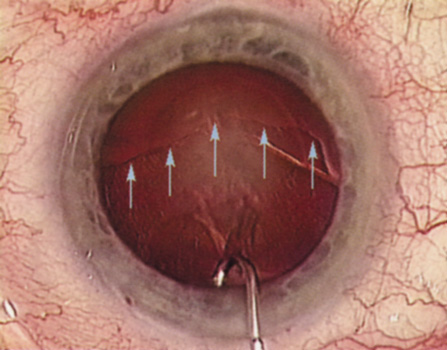

HYDRODISSECTION Hydrodissection can be performed after the surgeon has successfully completed capsulorrhexis.97 If the capsulorrhexis is not intact, fluid forced around the interior of the capsule may cause the bag to splay open. With capsulorrhexis, hydrodissection is a safe and extremely useful maneuver. Hydrodissection can be thought of as two maneuvers: hydrodelineation and cortical cleaving hydrodissection. By placing a 27-gauge cannula on a syringe filled with balanced saline solution (BSS), the surgeon can direct fluid beneath the residual anterior capsular rim to create a cleavage plane. Depending on the direction the fluid wave takes, different lamellae of the cataract will be separated. Hydrodelineation is the term used when the cleavage plane separates the adult nucleus from the fetal nucleus or the adult nucleus from the more peripheral epinucleus. Hydrodelineation often results in the characteristic golden ring sign (Fig. 11). Cortical cleavage occurs when the cortex is separated from the capsular bag (Fig. 12). Finding the cortical cleavage plane may be facilitated by gently lifting the capsular margin away from the cortex with the BSS cannula before injecting. Several small bursts of fluid allow the surgeon to monitor progress of the fluid wave. When dealing with a soft nucleus, the authors strive to perform true cortical cleaving hydrodissection. For a hard nucleus, hydrodelineation allows manipulation of less of the nuclear bulk, although the remaining epinuclear shell must be addressed in an additional step. Hydrodelineation is particularly useful if the nucleus is not freely mobile after cortical cleaving hydrodissection.